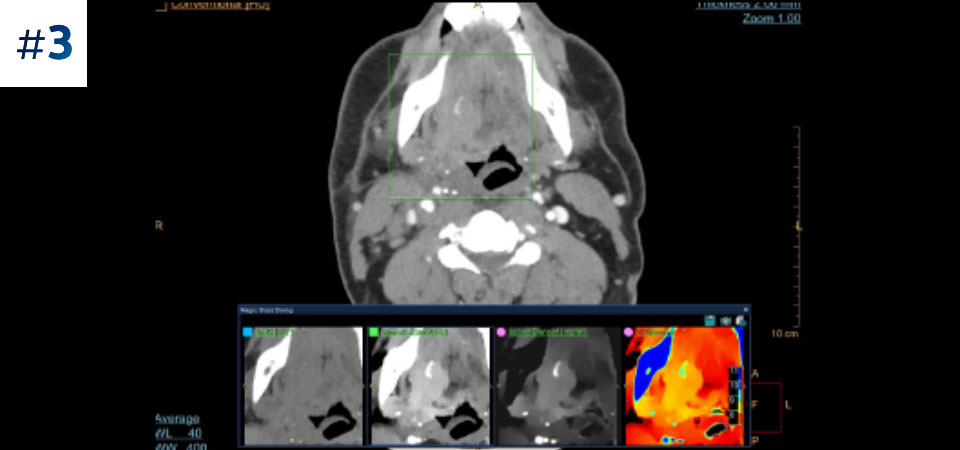

Neck mass